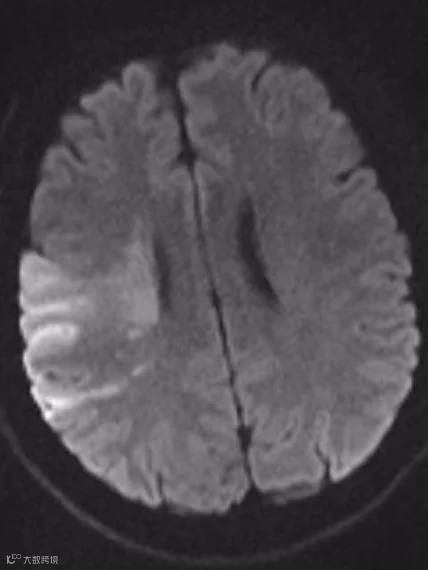

左图:梗死的脑组织

由于颈部没有骨头保护、很脆弱。当用力去按压颈部肌肉时,如果挤压到了动脉血管,则可能出现血管内膜层的撕裂,血液侵入血管管壁内导致壁内血肿,形成动脉夹层。

夹层在动脉血的冲击下越来越大,挤压正常的血管,使动脉血管狭窄甚至闭塞,或形成血栓脱落,导致远端脑血管堵塞而导致脑卒中。